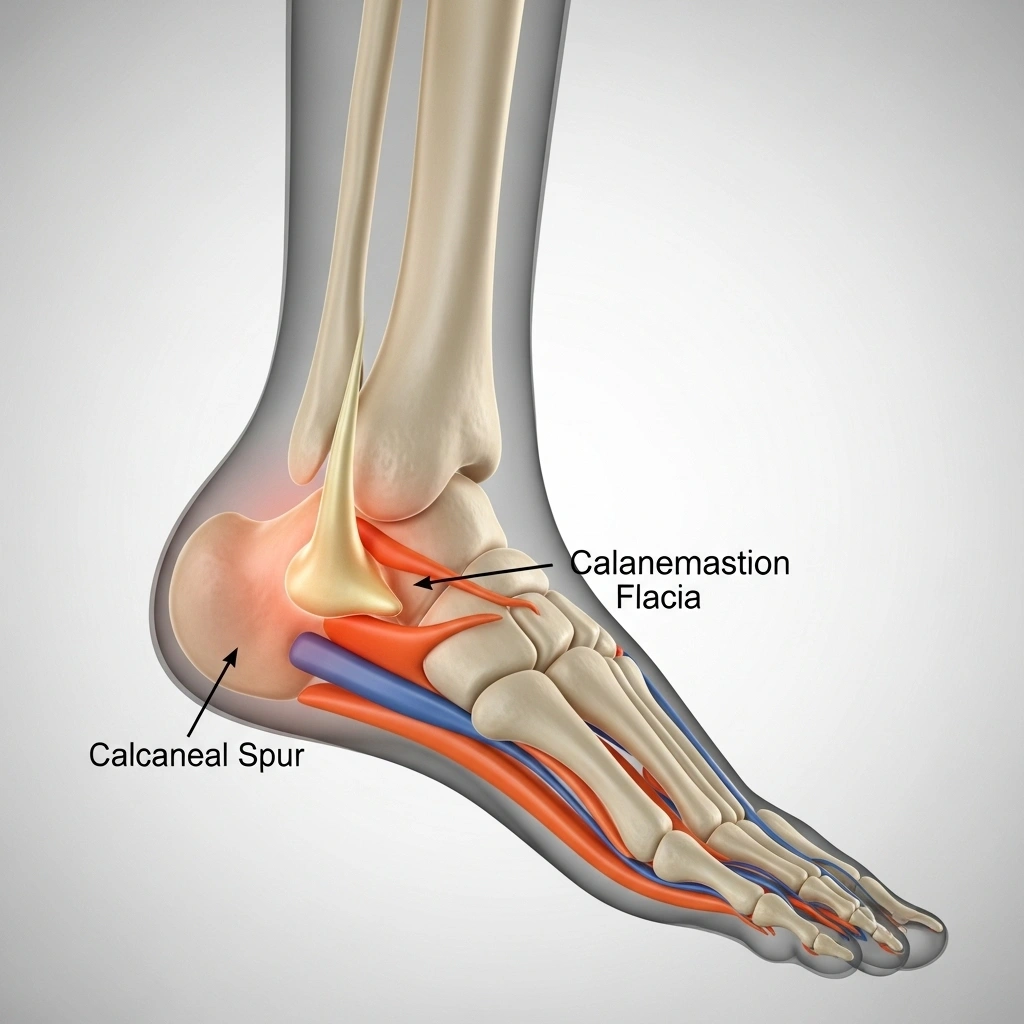

A calcaneal spur is a bony outgrowth on the underside of the heel bone (calcaneus). It develops due to calcium deposits and causes sharp, stabbing heel pain — especially during the first steps in the morning.

The bony spur can range from a small projection to over an inch long. It often accompanies plantar fasciitis — inflammation of the band of tissue running along the bottom of the foot — making every step a painful experience.